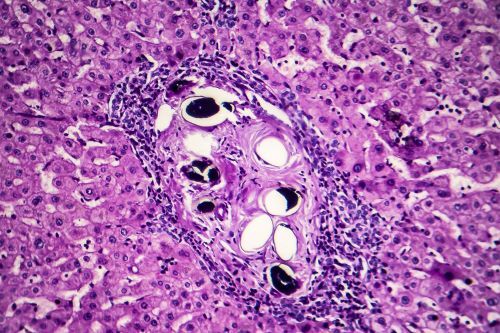

肝癌:我的預後和可能的治療方法是什麼?

肝癌可以分為不同的型別。

• 最常見的是HCCs或肝細胞癌,

• IHCs或影響膽管的肝內癌佔所有病例的10-20%

• 最罕見的是血管肉瘤,它影響肝臟血細胞的內壁,佔所有病例的1%

你的預後將取決於疾病進展的階段,以及癌症已轉移到多少器官。由於缺乏症狀,早期發現非常困難,除非定期進行預防性檢查。

治療方法可能包括栓塞術(阻斷腫瘤的血液供應)、消融術(在不切除腫瘤的情況下破壞腫瘤)或放射治療。